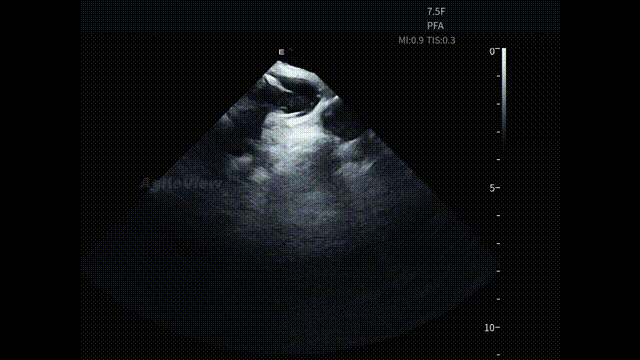

▶【房间隔穿刺与左房进入:路径清晰,节奏连贯】

在全球最细 7.5Fr ICE的持续影像引导下,术者完成房间隔穿刺。AgileView™ ICE实时显示房间隔 tenting及穿刺针跨隔过程,使穿刺路径和深度判断更加明确。穿刺成功后,PulseSelect™导管顺利进入左心房,整体操作节奏紧凑。

在另一台孙奇教授主刀的AgileView ™ ICE 结合冷冻球囊消融的手术中, ICE 也为后续 冷冻球囊导管跨间隔进入左房及空间定位提供影像支持,整体操作节奏紧凑、路径清晰。

房间隔穿刺(PulseSelect™手术)

房间隔穿刺(AFA冷冻消融手术)